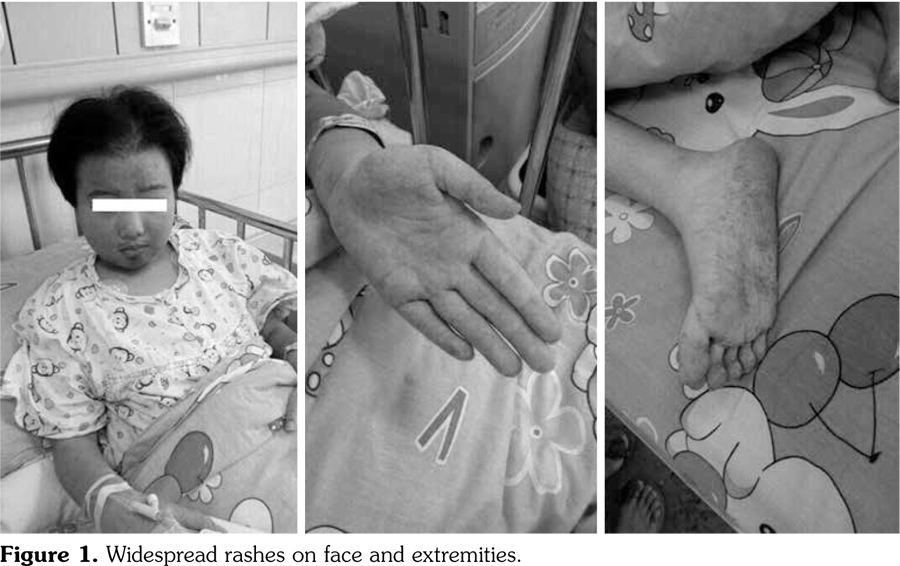

An 11-year-old girl was admitted to our department with a six-month history of anorexia and rashes on her face and extremities (Figure 1). On admission, her axillary temperature was 37.7°C, heart rate was 130 beats/minute, blood pressure was 82/47 mmHg, respiratory rate was 22 breaths/minute, and oxygen saturation was 95%. Cardiac examination revealed a soft systolic murmur at the apex with low heart sounds. She had malar rash, discoid rash, hepatosplenomegaly, and edema of the lower extremities. The subsequent autoimmune and serologic workup came back positive for anti- nuclear antibody at a titer of 1:3200, positive anti- double stranded deoxyribonucleic acid, anti-Smith antibody, and low complements (0.28 g/L) and complement 4 (C4) (0.03 g/L). Other laboratory studies exhibited anemia (red blood cell 3.1∞1012/L, hemoglobin 99 g/L), proteinuria (24-hour urine protein 300 mg/day), elevation of acute-phase reactants (C-reactive protein 132 mg/L, erythrocyte sedimentation rate 54 mm/hour), hyperamylasemia (208 units/L), hyperlipasemia (1556 units/L), and raised creatine kinase (CK, 375 units/L) and CK-MB (83 units/L). Electrocardiogram revealed sinus tachycardia with T wave inversion. Echocardiography showed normal left ventricular size but global hypokinesia with an ejection fraction of 37%. Abdominal computed tomography demonstrated swollen pancreas but no gallbladder stones (Figure 2). Renal biopsy revealed diffuse proliferative glomerulonephritis Class IV-G. Our patient was diagnosed as having systemic lupus erythematous (SLE) complicated by pancreatitis and myocarditis. SLE disease activity index score was 24. She was treated with a course of pulse methylprednisolone 10 mg/kg/day for three days and subsequently converted to oral prednisone (60 mg/day). In addition, several symptomatic treatments such as bowel rest, nutritional support, somatostatin, and fructose-1,6-diphosphate were also adopted. One month later, intravenous cyclophosphamide 500 mg/m(2) was given. Two months later, repeated echocardiography showed a marked improvement in ejection fraction, abdominal computed tomography revealed a less swollen pancreas, and SLE disease activity index score was 2. The patient was discharged with normal pancreatic (amylase 109 units/L, lipase 285 units/L) and myocardial enzymes (CK 29 units/L, CK-MB 11 units/L).

Systemic lupus erythematous is a chronic, autoimmune disease characterized by the presence of a plethora of autoantibodies, immune complex formation, and multiple organ involvement. The American Rheumatism Association criteria for SLE are still the most commonly used criteria for diagnosis.(1) In this report, our patient fulfilled six criteria (malar rash, discoid rash, renal disorder, hematologic disorder, immunologic disorder, and anti-nuclear antibody), thus the diagnosis of SLE could be established undoubtedly. The major reason triggering us to present this case was the co-existed myocarditis and pancreatitis secondary to SLE. Secondly, C-reactive protein was skyrocketing in parallel with multiple organ dysfunction. An Indian retrospective study enrolling 141 SLE cases suggested that a positive correlation was observed between C-reactive protein and SLE disease activity index.(2) Therefore, C-reactive protein can reflect the disease activity of SLE to some extent.